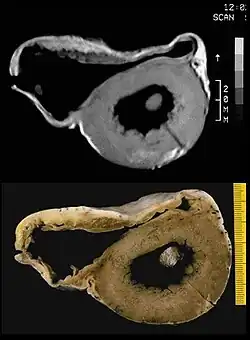

Linksventrikuläre Hypertrabekulation

Angeborene, seltene Herzmuskelerkrankung mit schwammartig aufgetriebener Muskulatur vor allem in der Spitze der linken Herzkammer, die tiefe Aushöhlungen (Sinusoide) zwischen Muskelfasern (Trabekeln) aufweist, die mit der Herzhöhle verbunden sind. Bei der Isolierten Nonkompaktion des Herzmuskels (Syn: Non-Compaction-Kardiomyopathie, linksventrikuläre Hypertrabekulation, spongy myocardium) hat sich der Herzmuskel aus seinem losen Maschennetz während der frühen Embryonalphase nicht weiter verdichtet (schwammiges Myokard). Gehäuft bei Skelettmuskelerkrankungen, auch in Kombination mit komplexen zyanotischen Herzfehlern.

Die Diagnose wird durch Echokardiografie, MRT oder Angiografie der linken Herzkammer bei einer Herzkatheteruntersuchung gestellt. Unklar ist der klinische Verlauf. Fälle von schwerem Herzversagen, Thromboembolie, Arrhythmien und plötzlichem Herztod sind bekannt. Familiär gehäufte Fälle wurden beschrieben, wobei Mutationen der Z-Scheibe, der Mitochondrien und des G4.5-Gens für Tafazzin isoliert werden konnten.[8]